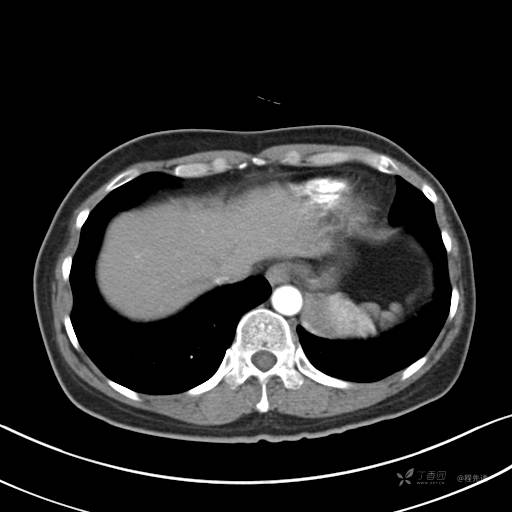

CT平扫

病灶平扫CT值约31HU